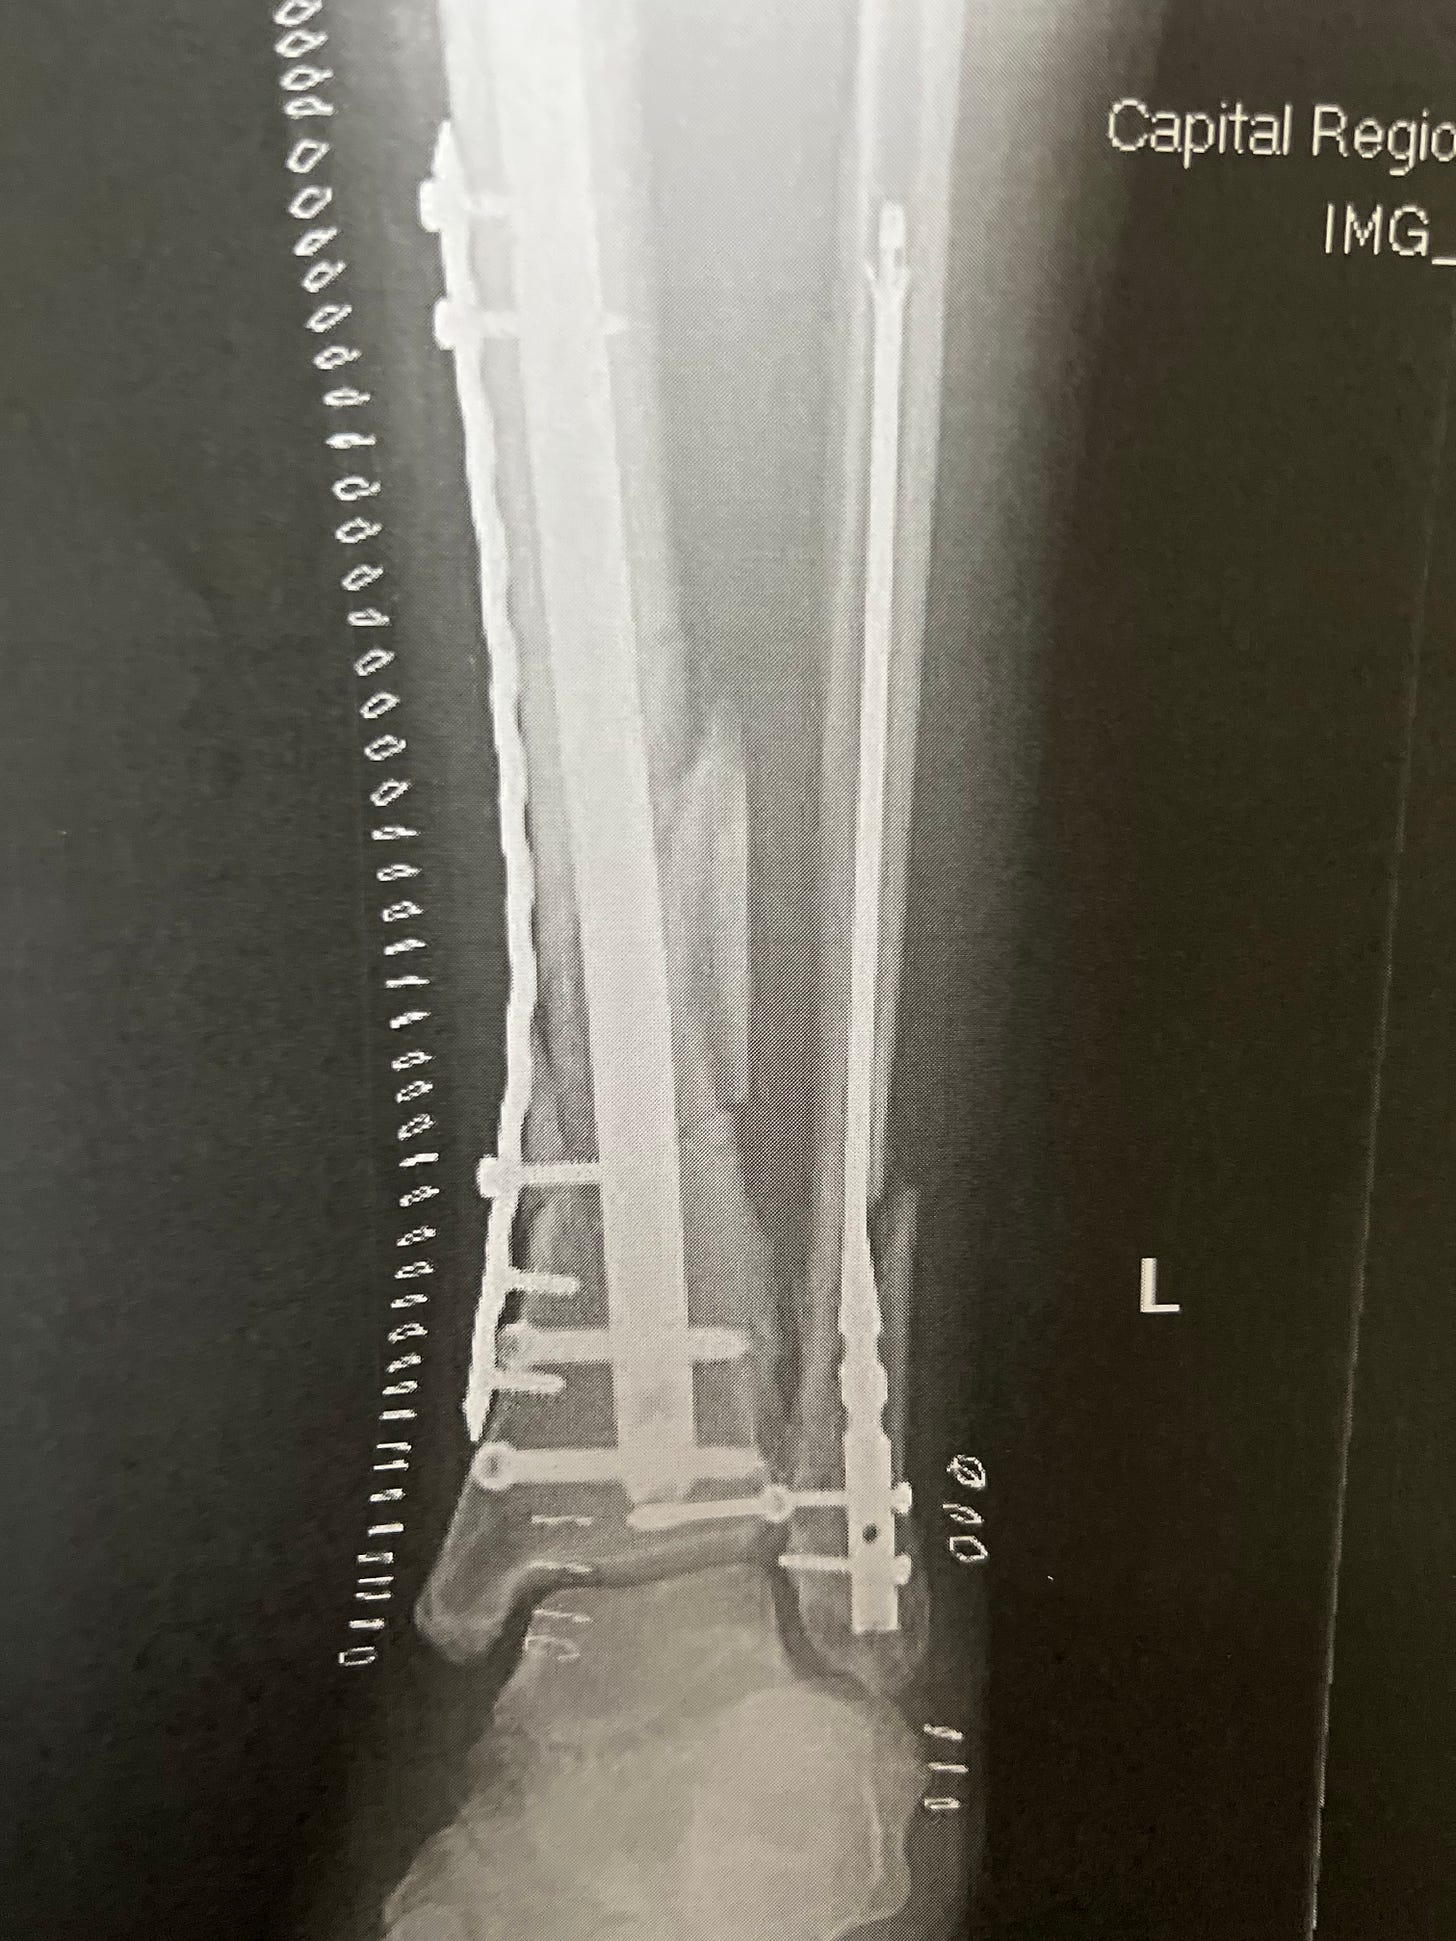

I slipped on ice in our office parking lot and badly fractured both the tibia and fibula in my left leg. I now hold the honor of having broken the same leg three times: 1975, 1999 and 2022.

Because of the severity of the trauma (and an intervening weekend), it took four days for the first surgery to occur, and then another week before the second and final round of fixing. In between, my leg was supported by an erector set to keep it stable and reduce the swelling. I now live with a permanent collection of titanium parts: rods, plate and screws as noted in the picture above.